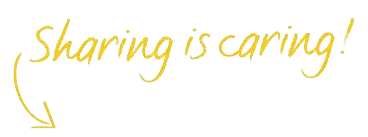

Selain kekurangan cairan dalam tubuh atau kekurangan mineral tertentu, kondisi lain seperti menyempitnya rongga antartulang belakang (stenosis spinal) dan terjepitnya saraf tulang belakang (hernia nukleus pulposus/HNP) juga dapat menyebabkan kram pada kaki.

Selain kram, gejalanya juga disertai dengan kesemutan, kebas dan bahkan bila tidak mendapatkan penanganan yang tepat dapat mengakibatkan kelumpuhan.

Kedua kondisi tersebut memerlukan penanganan medis lebih lanjut agar keluhan kram pada kaki menjadi reda atau menghilang.